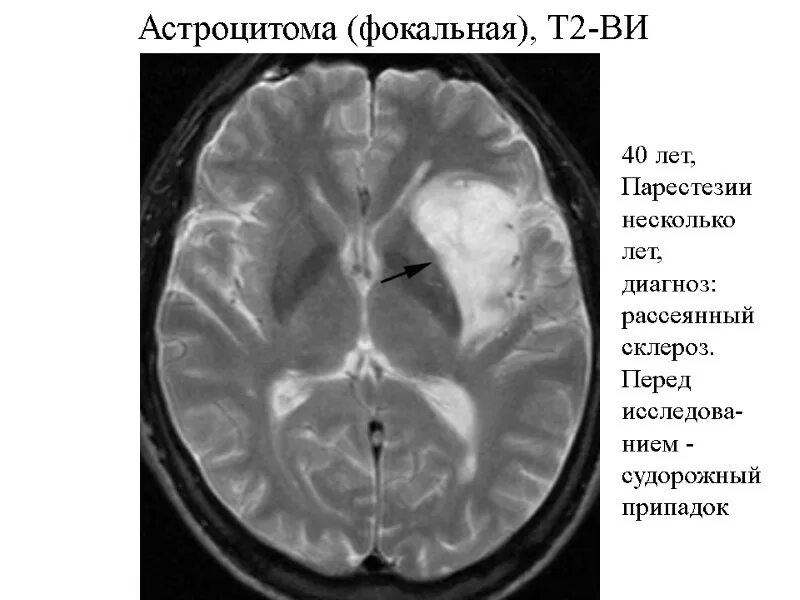

Астроцитома головного мозга прогноз после операции